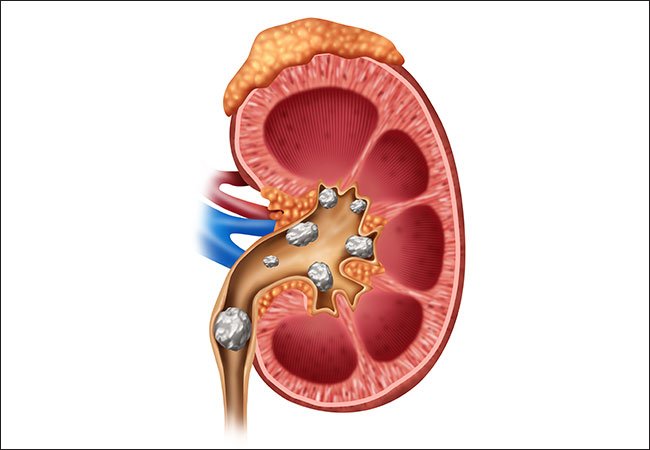

- Kidney stones.